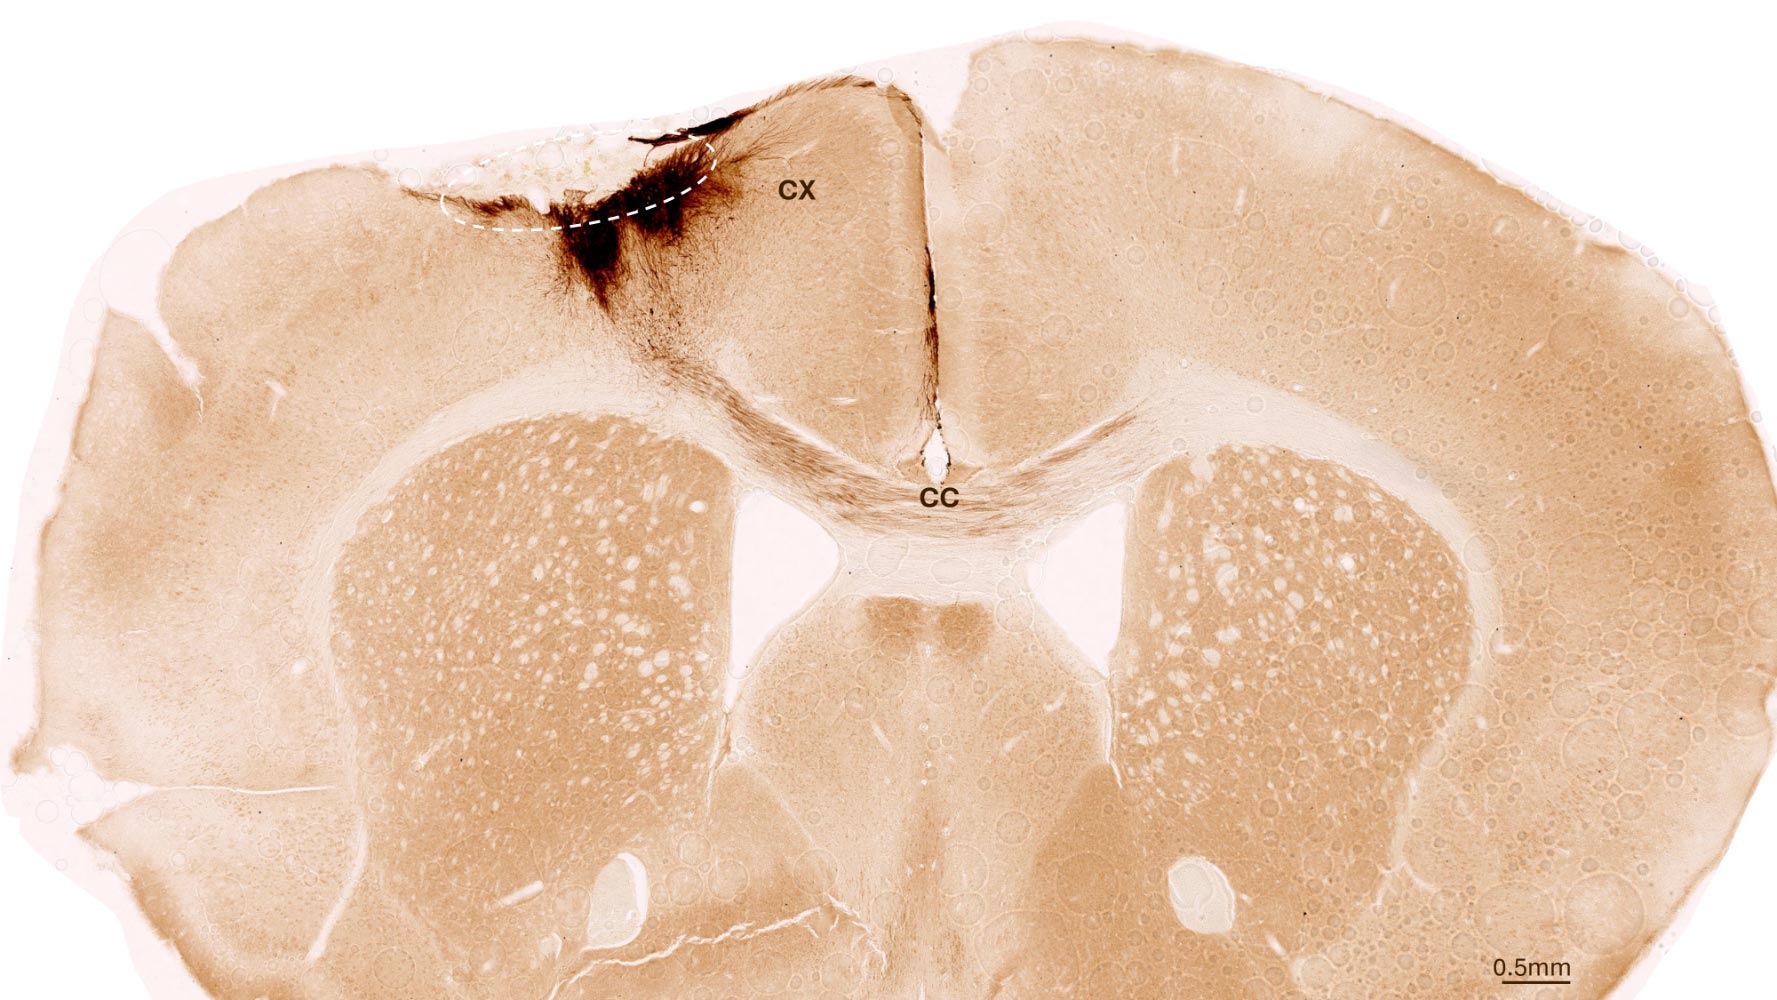

Stem cell therapy in mice has successfully reversed stroke damage by regenerating neurons and improving motor function, bringing us closer to potential human treatments for brain injury recovery.